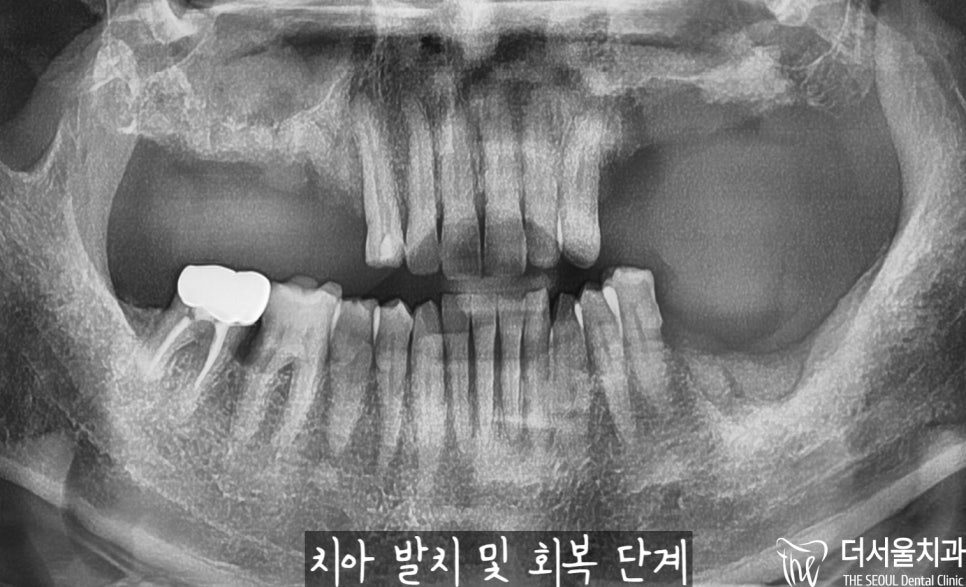

더 정확한 진단을 내릴 수 있도록

태평동 치과 에서는

파노라마(X-Ray) 촬영에 들어갔습니다.

예측했던 것보다

더 상황은 좋지 않았습니다.

우선 10번대를 살펴보면 치근단 염증으로

뿌리 끝에 거멓게 변해있는 것을

볼 수 있으실텐데요.

이미 골소실이 많이 일어났고,

그 영향으로 이가 흔들릴 수밖에 없었습니다.

20번대 또한 마찬가지로

심하게 뼈를 잃게 되었으며,

그 영향으로 치아 흔들림이

나타날 수밖에 없었습니다.

30번대 어금니 또한 마찬가지,

뿌리 끝에 염증이 심하여

뼈가 사라져 치아 흔들림이